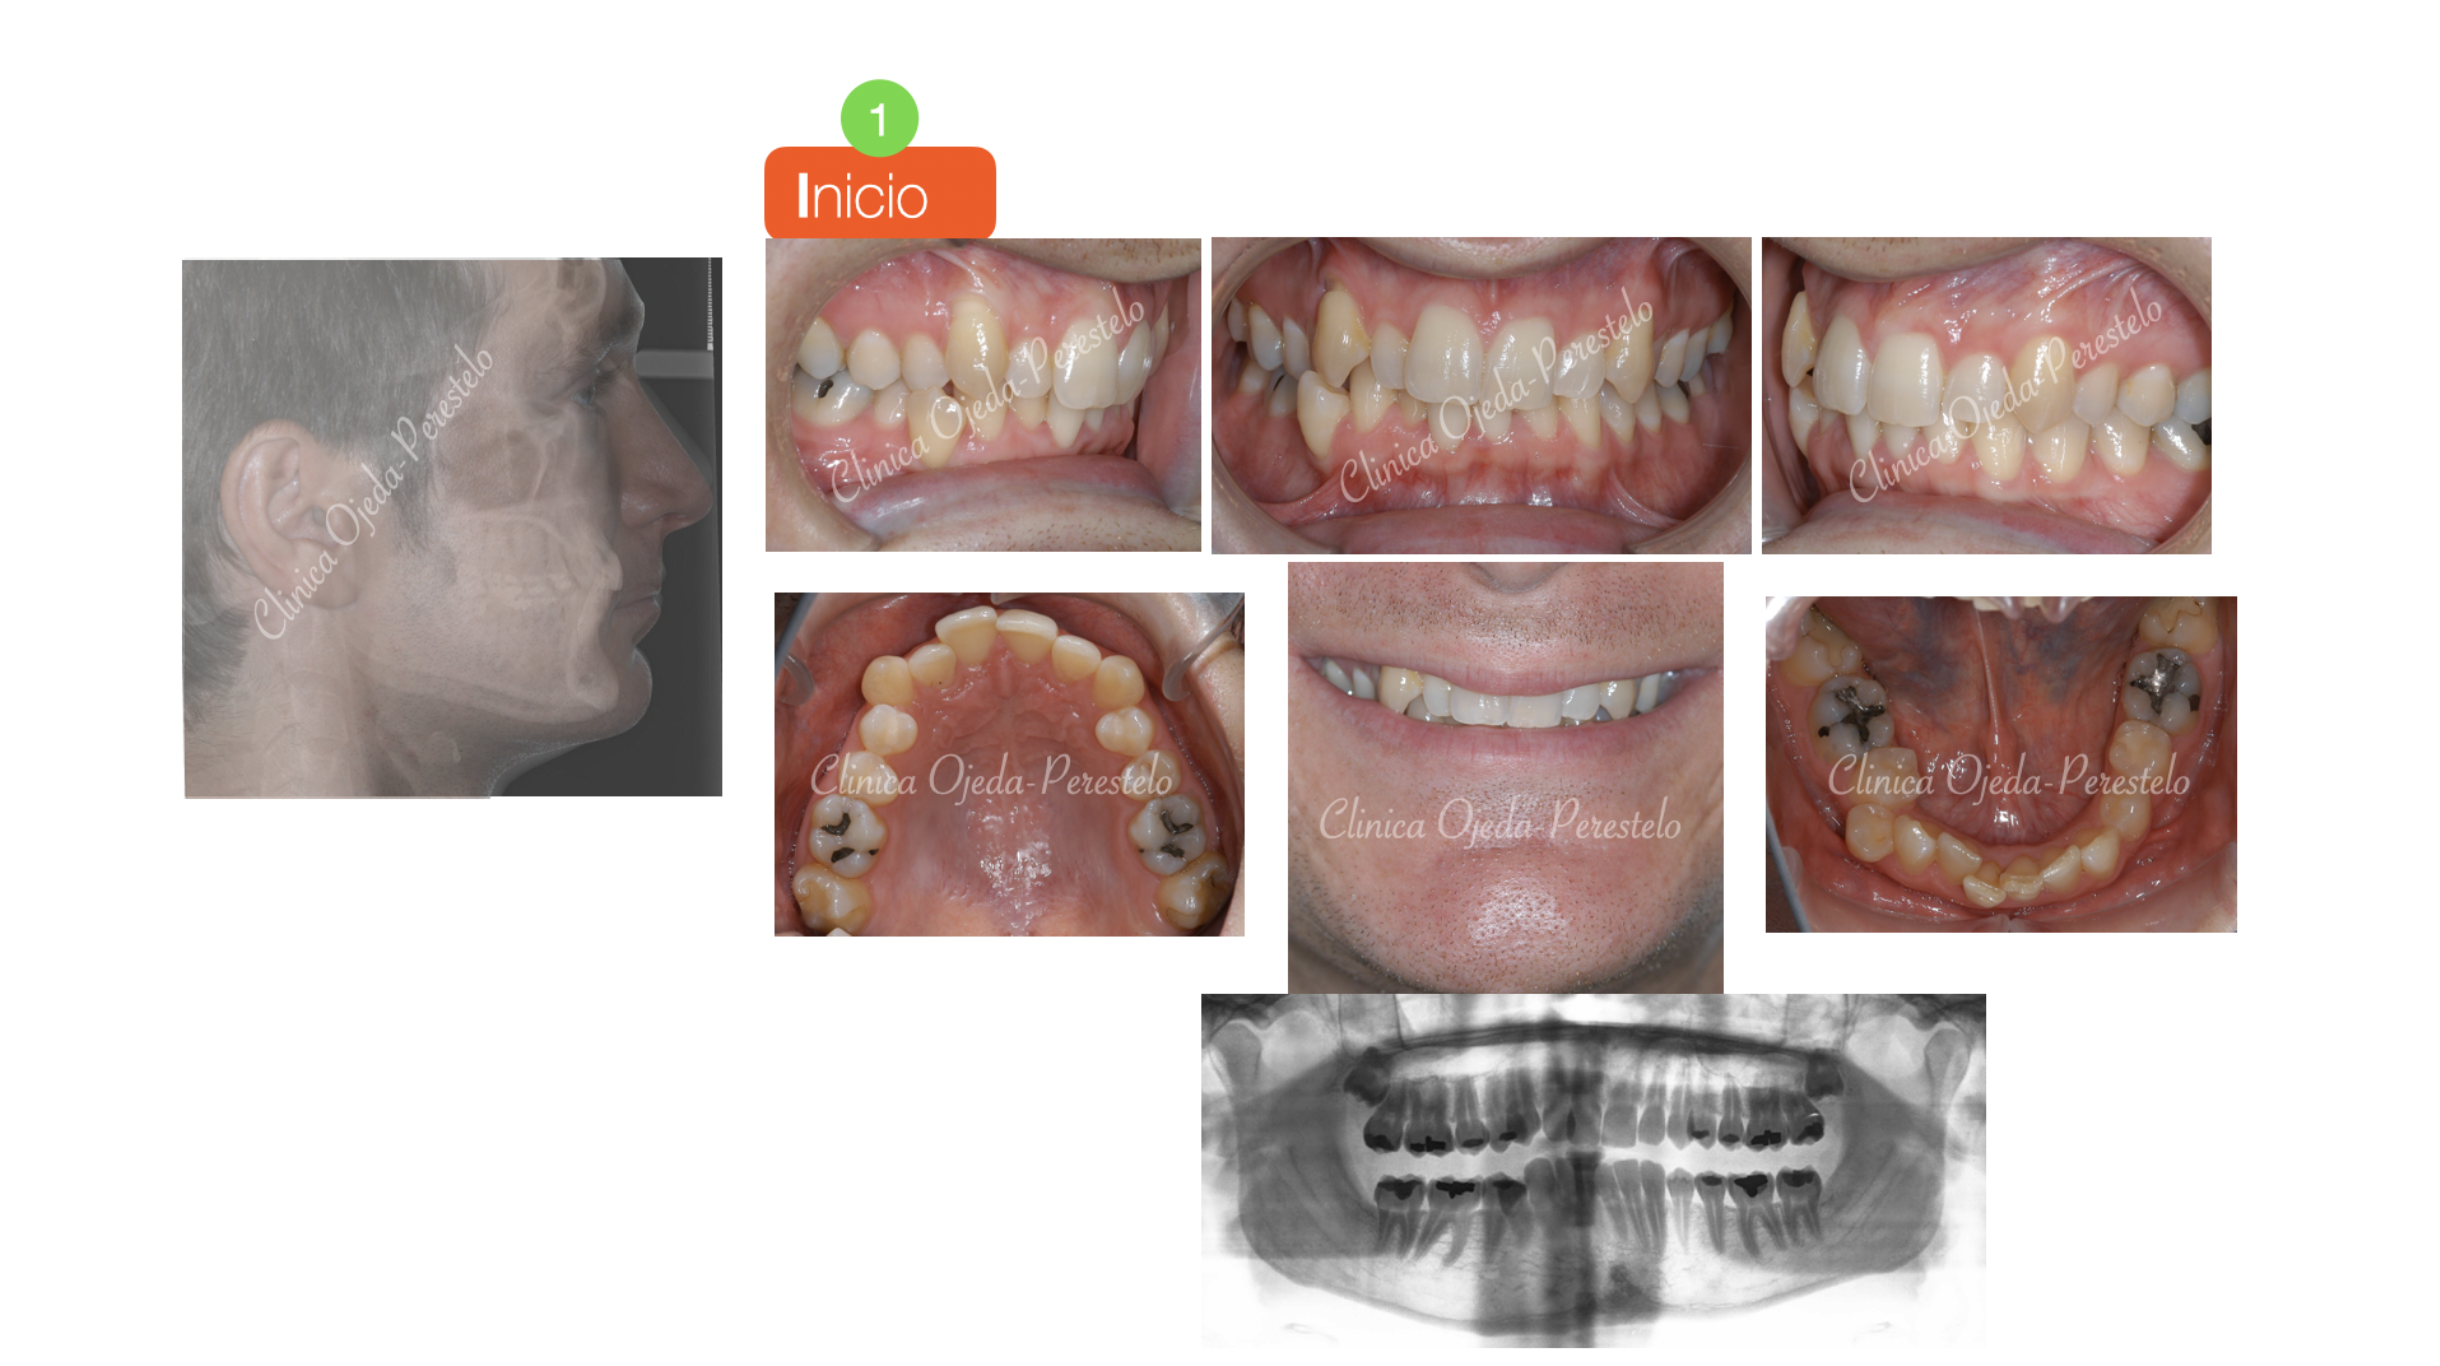

Caso Ortodoncia Lingual Superior con Vestibular Inferior

Presentamos un caso tratado con brackets superiores colocados por lingual y brackets inferiores por vestibular,opción preferida por la mayoría de los pacientes, donde nuestros objetivos fueron:

-1. Alinear y nivelar las arcadas sin extracciones.

-2. Intercuspidar correctamente ambos maxilares.

-3. Dotarle de una mayor amplitud a la sonrisa.

Queremos destacar la gran mejoría en la sonrisa y en el correcto engranaje dentario (articulación dentaria) observado en este paciente.